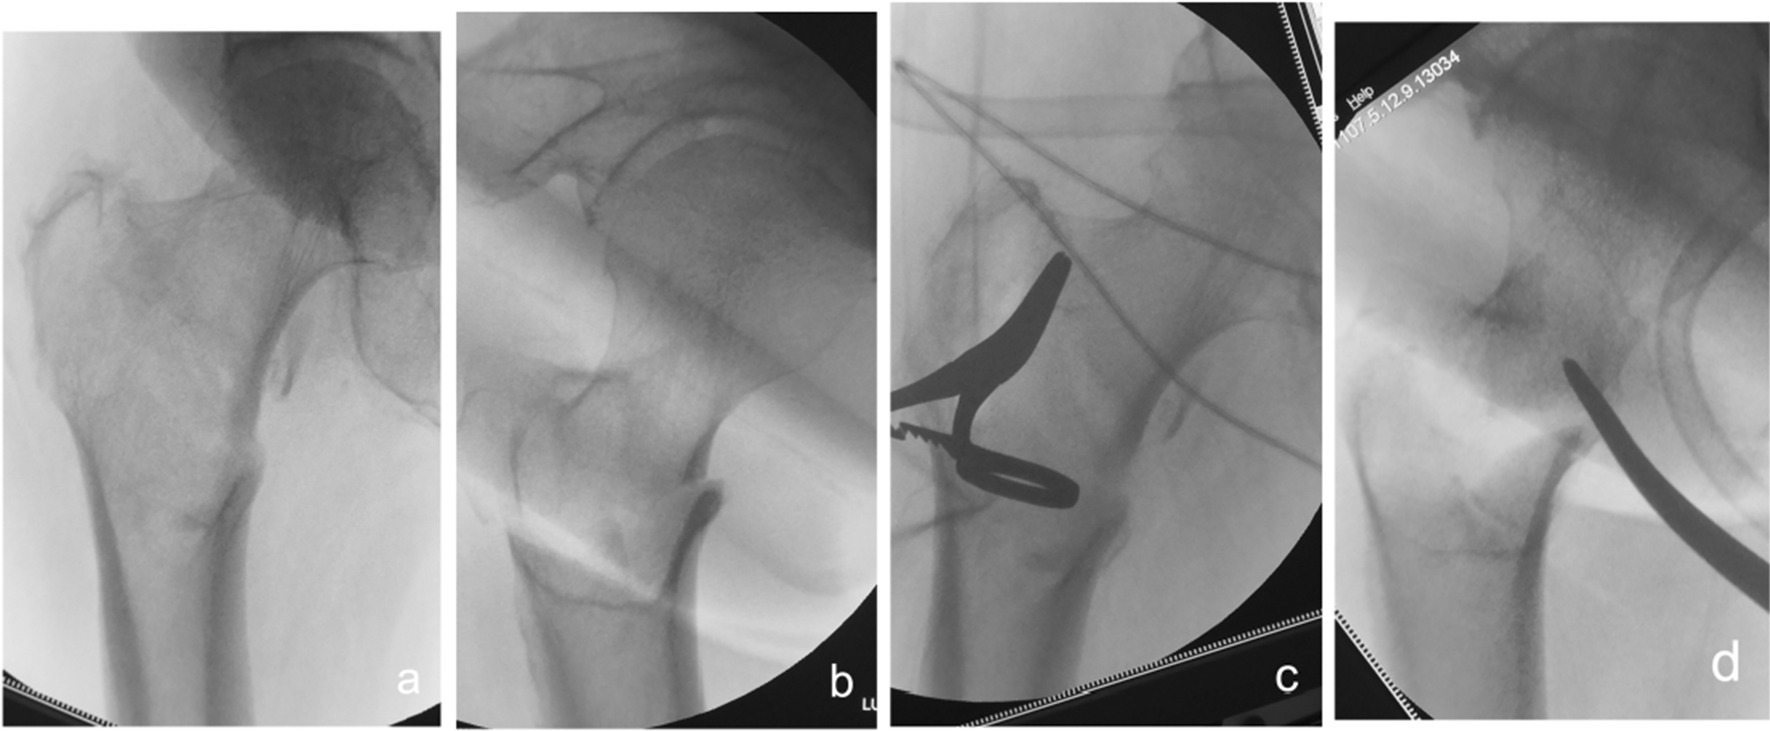

Fig. 5.

Anteroposterior and lateral X-ray films before and after reduction in patients with difficulty in reduction on the coronal plane and internal rotation displacement of the proximal fracture segment a, b Before reduction; c, d After reduction (one head placed on the inner side of the proximal fracture segment and the other head on the outer side of the greater trochanter)

Fig. 6.

Anteroposterior and lateral X-ray films before and after reduction in patients with difficulty in reduction on the coronal plane and external rotation displacement of the proximal fracture segment a, b Before reduction; c, d After reduction